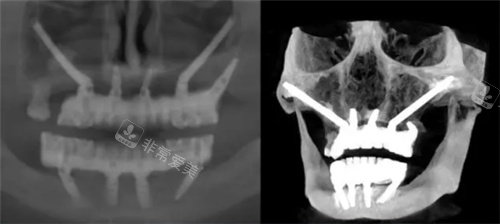

穿颧穿翼种植牙图示

穿颧穿翼CT图示